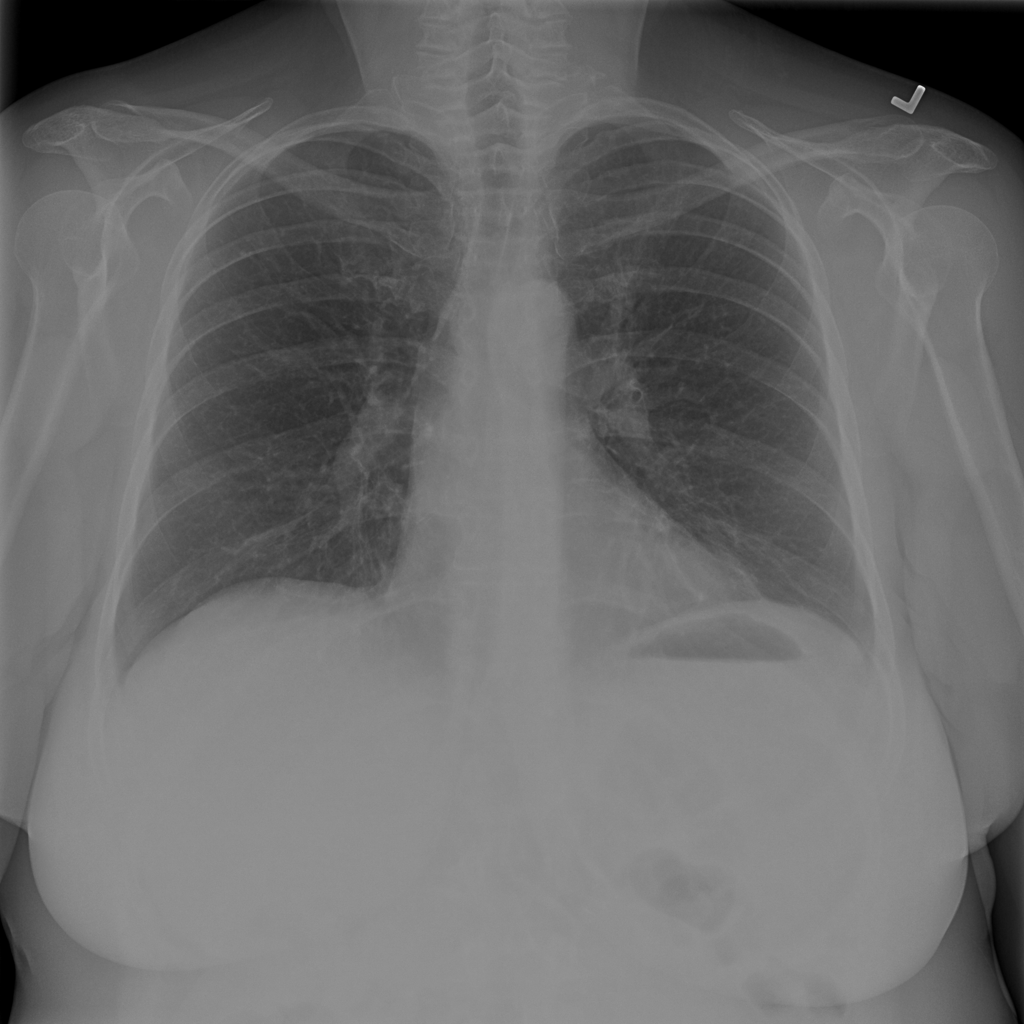

Nodule

A nodule is a small rounded opacity in the lung or chest field. It is a descriptive imaging finding that can be benign or more concerning depending on size, appearance, and context.

Showing up to 90 reference images for Nodule.